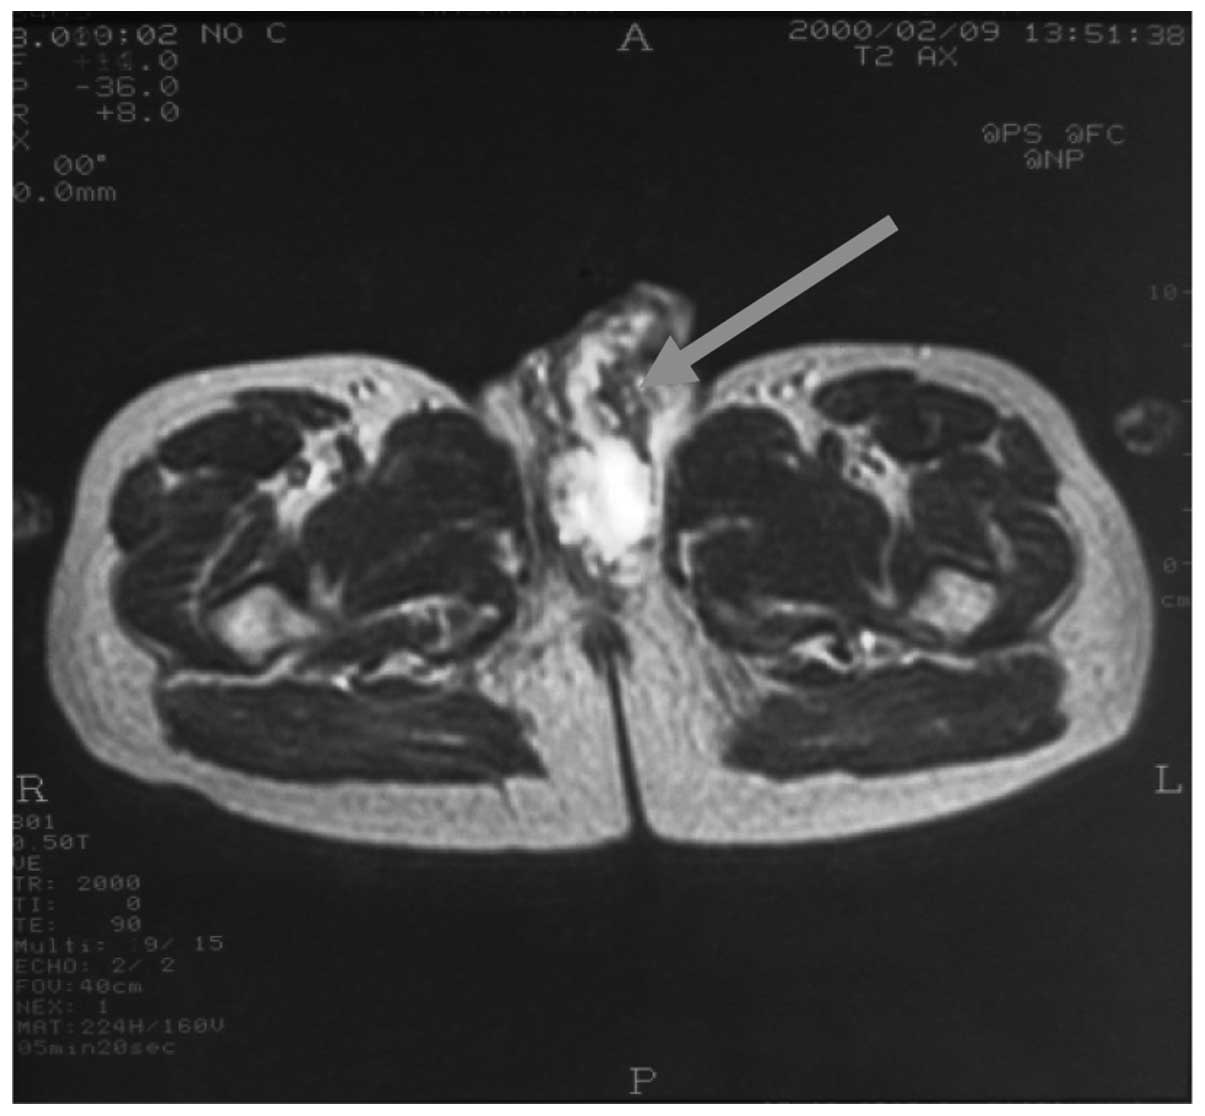

penile cancer photos download

Posts: penile cancer photos download